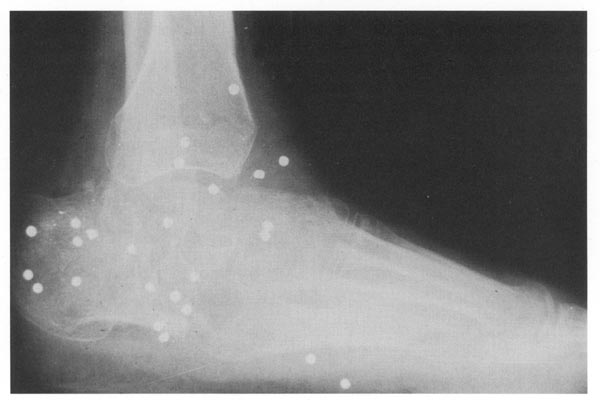

perdigo.jpg (31264 bytes)

Perdigones alojados en las manos